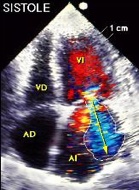

Técnica doppler:

- Para valorar el flujo se utiliza el doppler color:

- Se detecta insuficiencia mitral, que suele ser ligera o moderada. No es la causa primaria de la miocardiopatía.

Doppler color